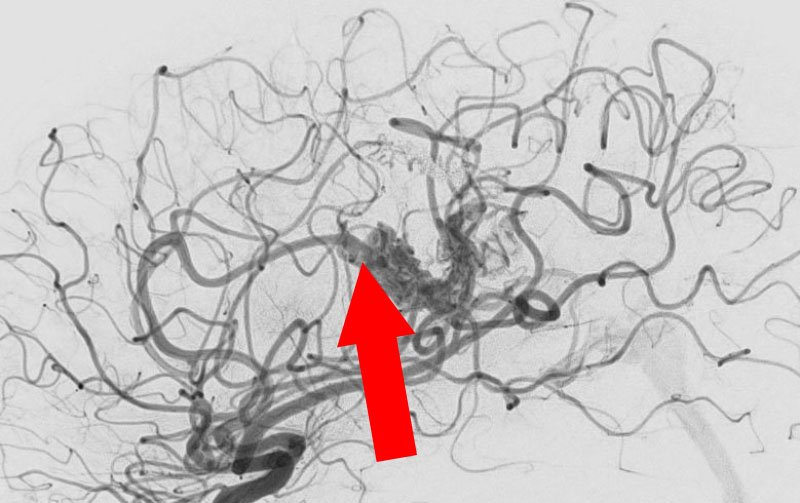

No.1620 手術中